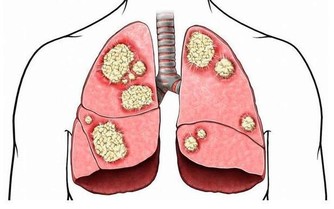

吸煙,會加重胃炎、潰瘍病的病情,不利於胃炎、潰瘍病的康復。

據研究發現,吸煙者,潰瘍病的發病率,是非吸煙者的2-4倍。

每天吸煙20支以上的人,約40%可發生胃粘膜炎症。

酒精入胃,會直接損害胃粘膜,甚至引起炎症、癌變。

酒精度數越高,對於胃部的損害也就越嚴重,養護胃部要注意少碰酒飲。

所以,養護肺部健康,要戒菸忌酒。